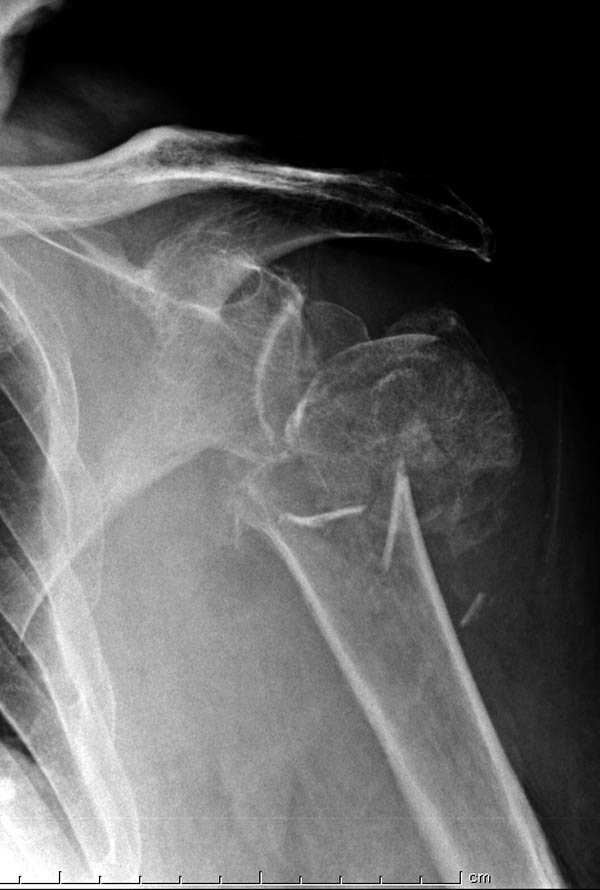

Здесь пример открытой репозиции 57 летнего с переломом плеча (1,2) смещение обнаружено на интероперационном снимке. При нормальной прямой проекция (3) угловое смещение обнаружили в аксиальной проекции (4)

После устранения смещения пластина установлена выше (5,6,7) и финальные снимки (8,9,10)